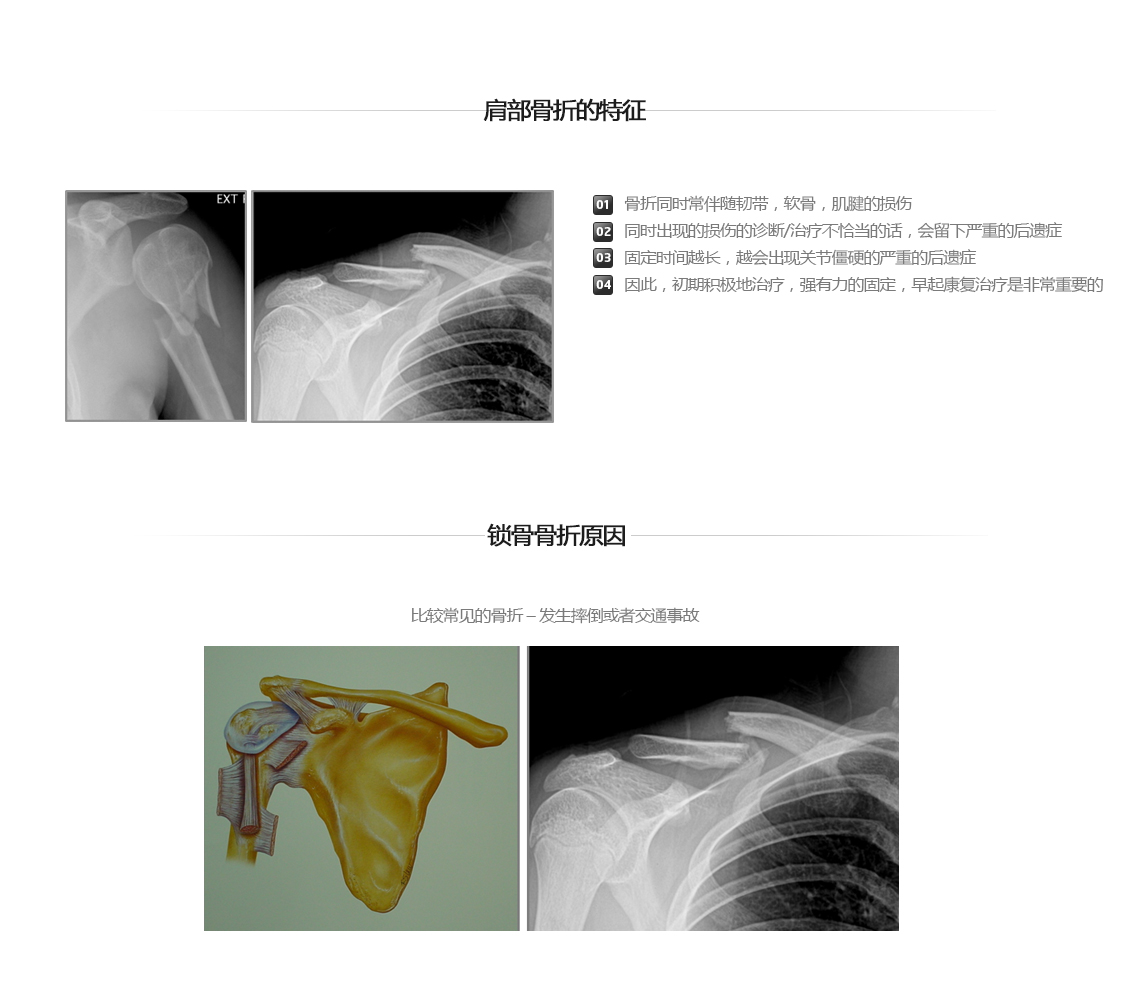

肩部关节的外伤